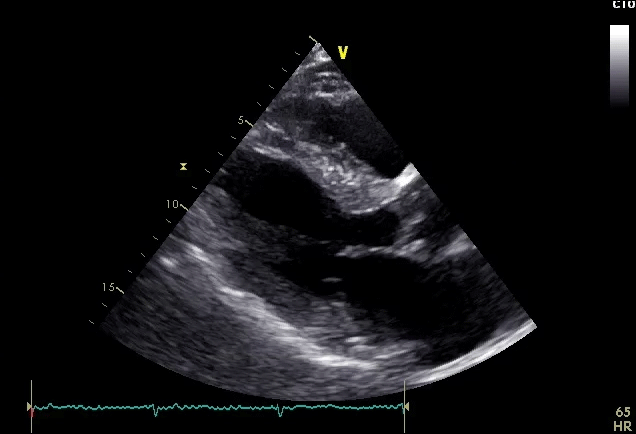

ATTR-CM é uma doença rara, progressiva, infiltrativa, de risco à vida, que muitas vezes pode ser subestimada como causa de insuficiência cardíaca. Proteínas transtirretina ( TTR) com estruturas instáveis que se dobram de forma incorreta e se agregam em fibrilas amiloides, e se depositam no coração e em outros órgãos. 1-3 É fundamental reconhecer as pistas diagnósticas para que você possa identificar a doença.